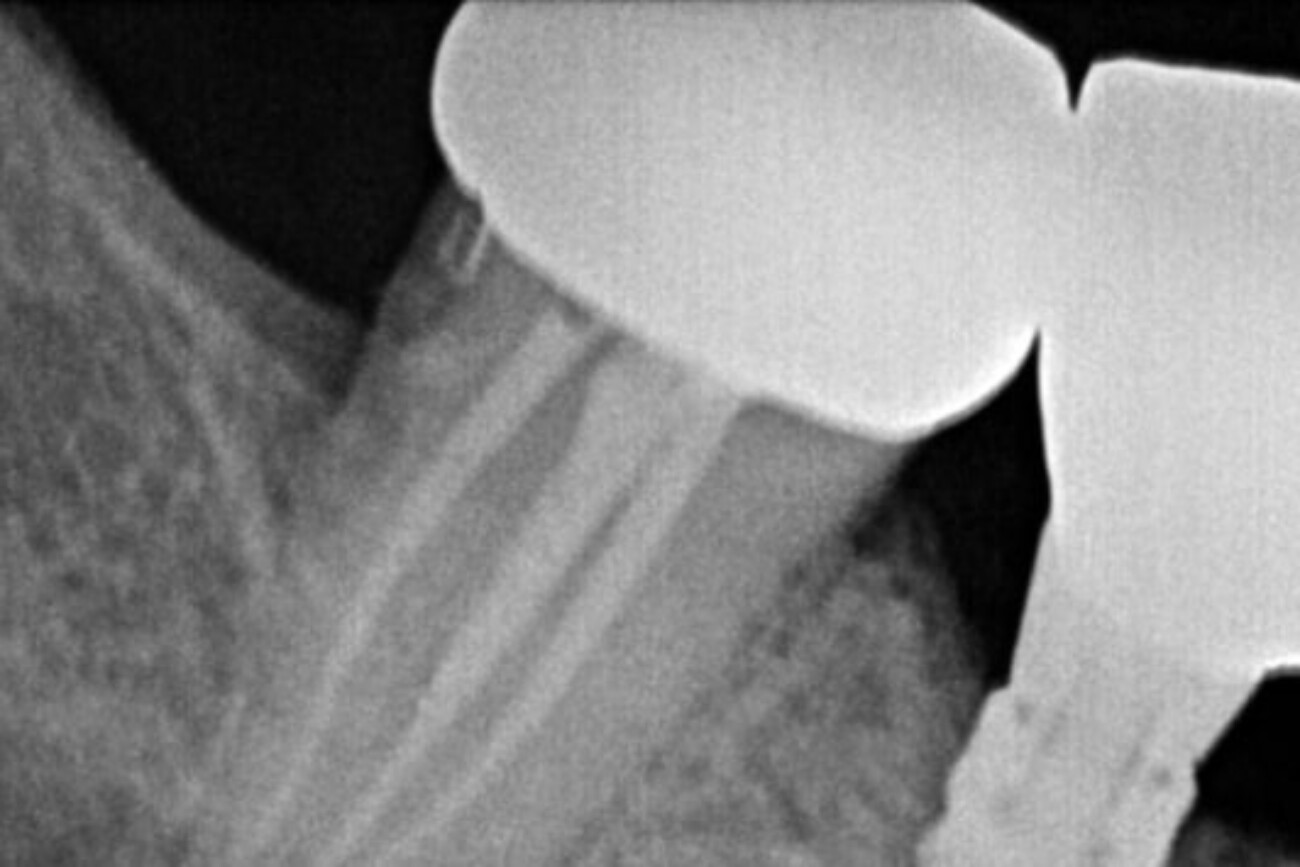

State-Of-The-Art Technology For

Root Canal In Tijuana

By incorporating advanced technologies, XDentistry ensures that root canal treatments are not only efficient but also highly precise, tailored to each patient’s unique dental needs. This commitment to cutting-edge advancements guarantees optimal outcomes and patient satisfaction.

3D CBCT for Teeth Scanning:

Providing detailed 3D images of the teeth and surrounding structures. This aids in diagnosing complex root canal cases by offering a comprehensive view, enabling precise treatment planning.